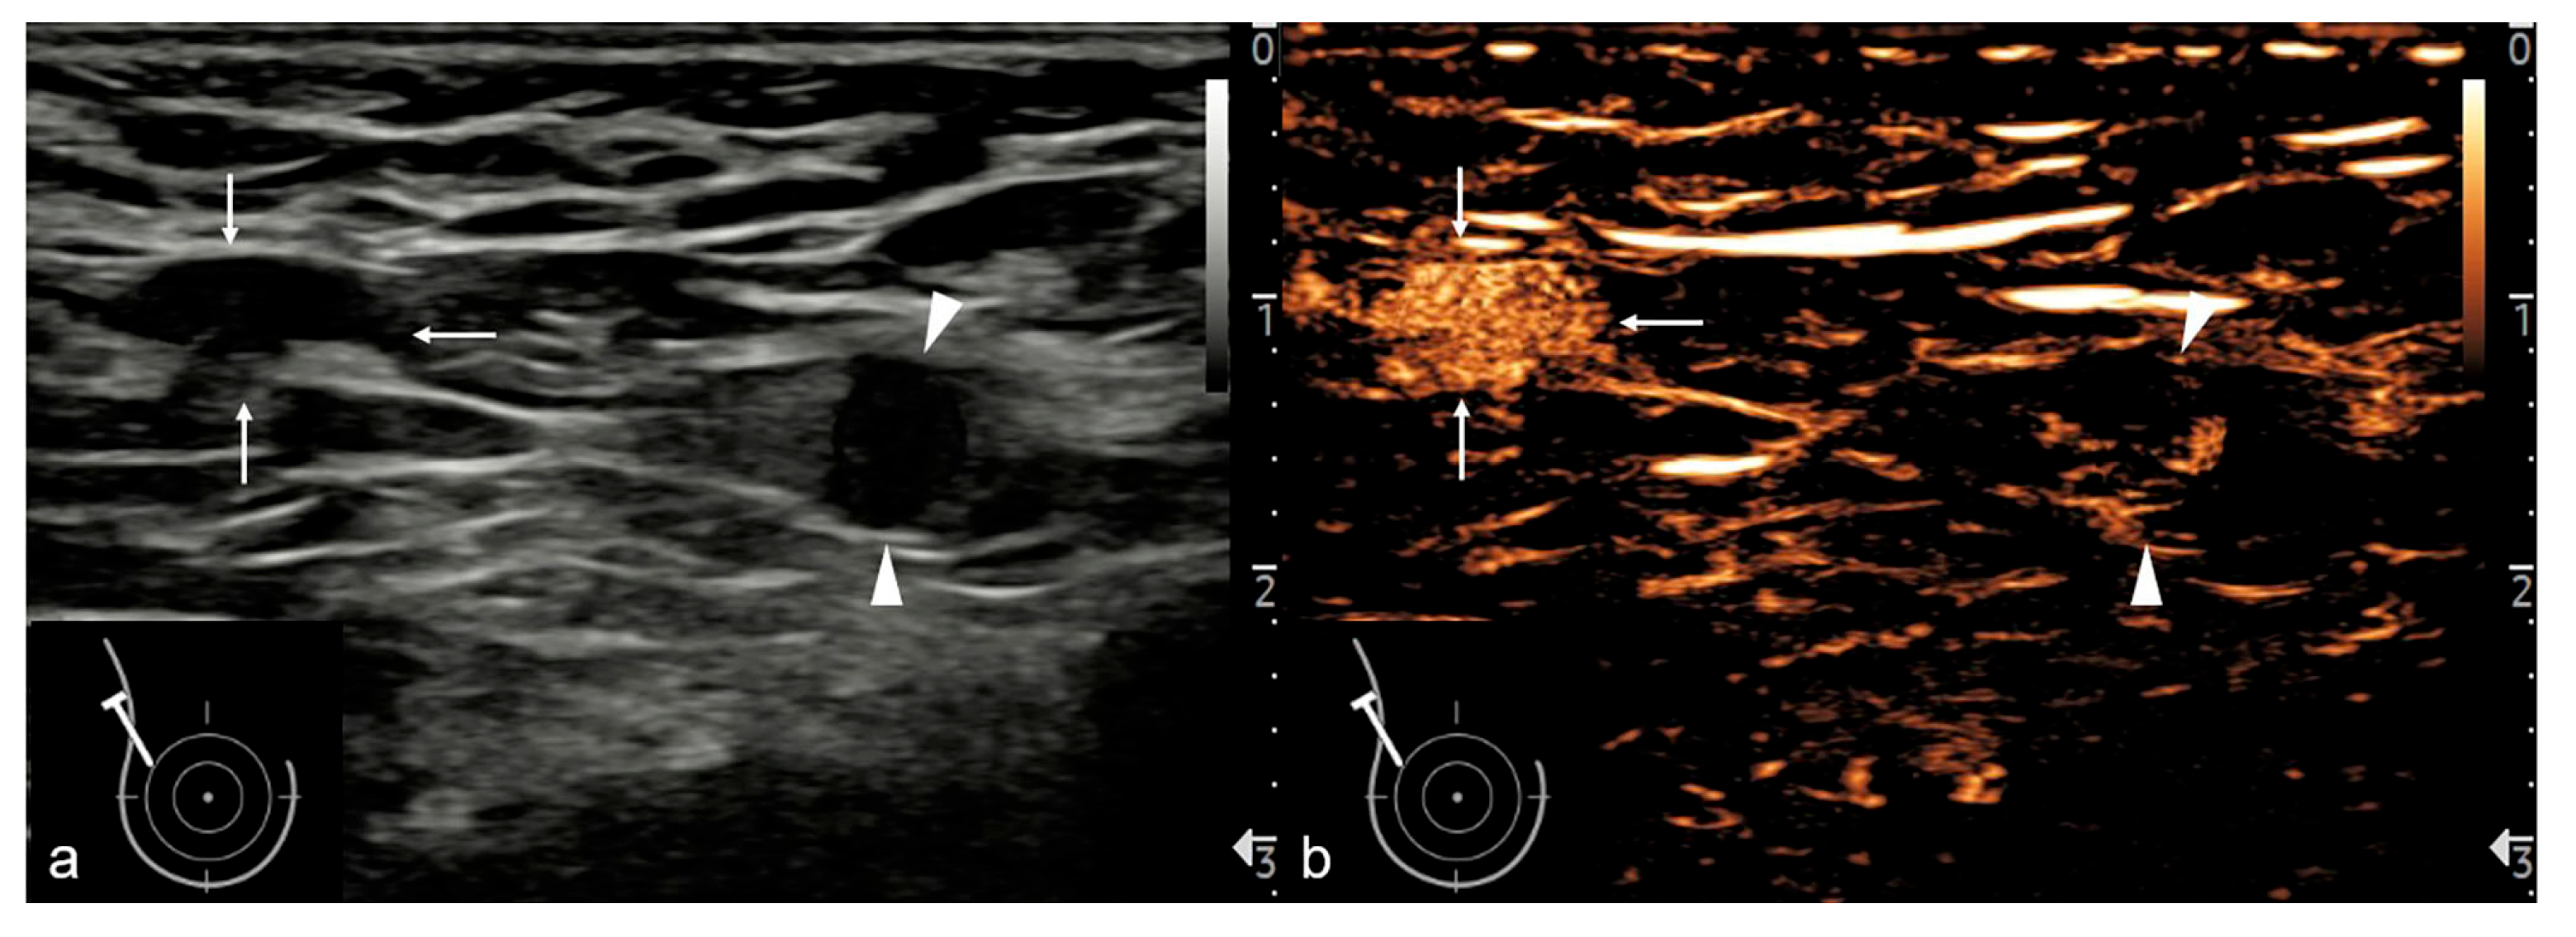

| The vascular phase | Intravenous | Sonazoid | 0–1 min | Enhancement homogeneity; perfusion defects; perfusion pattern |

| The postvascular phase | Intravenous | Sonazoid | 7–9 min | Enhancement degree; enhancement pattern; mean postvascular phase intensity |

| Conventional US | ||||

| L/S | 8.44 | 0.004 ** | ||

| <2 | 43 (65.15%) | 10 (33.33%) | ||

| ≥2 | 23 (34.85%) | 20(66.67%) | ||

| Hilum | 12.41 | <0.001 *** | ||

| Absent | 41 (62.12%) | 7 (23.33%) | ||

| Present | 25 (37.88%) | 23 (76.67%) | ||

| Cortical thickness, mm | 9.95 | 0.002 ** | ||

| ≥3 | 64 (96.97%) | 22 (73.33%) | ||

| <3 | 2 (3.03%) | 8 (26.67%) | ||

| The vascular phase | ||||

| Enhancement homogeneity | 22.68 | <0.001 *** | ||

| Heterogeneous | 45 (68.18%) | 4 (13.33%) | ||

| Homogeneous | 21 (31.82%) | 26 (86.67%) | ||

| Perfusion defects | 14.90 | <0.001 *** | ||

| Present | 33 (50.00%) | 2 (6.67%) | ||

| Absent | 33 (50.00%) | 28 (93.33%) | ||

| The postvascular phase | ||||

| Degree of enhancement | 58.04 | <0.001 *** | ||

| Relative hypo-enhancement | 64 (96.97%) | 6 (20.00%) | ||

| Relative hyper-enhancement | 2 (3.03%) | 24 (80.00%) | ||